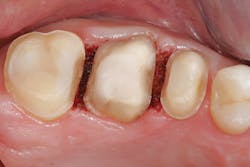

Figure 3: When the patient returned, e.max crowns were bonded with Variolink Esthetic Dual Cure (Ivoclar Vivadent), and the Picasso Lite laser (AMD Lasers) was used to achieve ideal isolation. The buildups and fillings were done with the same materials, Tetric EvoCeram Bulk Fill and Tetric EvoFlow Bulk Fill, allowing for more efficient quadrant dentistry. The same adhesive, Adhese Universal, was used for the fillings, buildups, and bonding of the restorations.

Figure 4: Immediately after bonding, the postoperative results were ideal contact areas and improved esthetics.